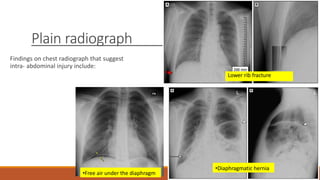

Plain radiograph

Findings on chest radiograph that suggest

intra- abdominal injury include:

Lower rib fracture

•Diaphragmatic hernia

•Free air under the diaphragm